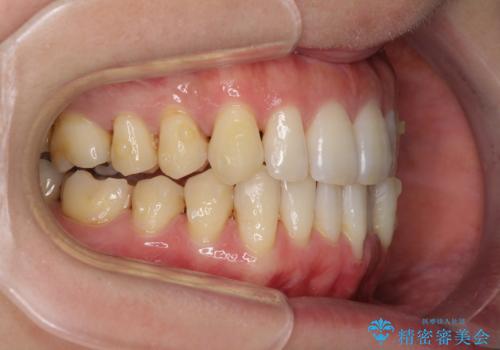

八重歯のインビザライン矯正治療

- 下顎の八重歯と、上下のクロスバイトを気にして来院された患者様です。

インビザラインを用い、下顎全体の後方移動、IPR(歯と歯の間を削る)と歯列全体を拡大させることで、歯並びを整えていくこととしました。